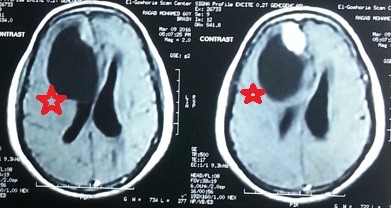

meningioma of the right lobe of the brain